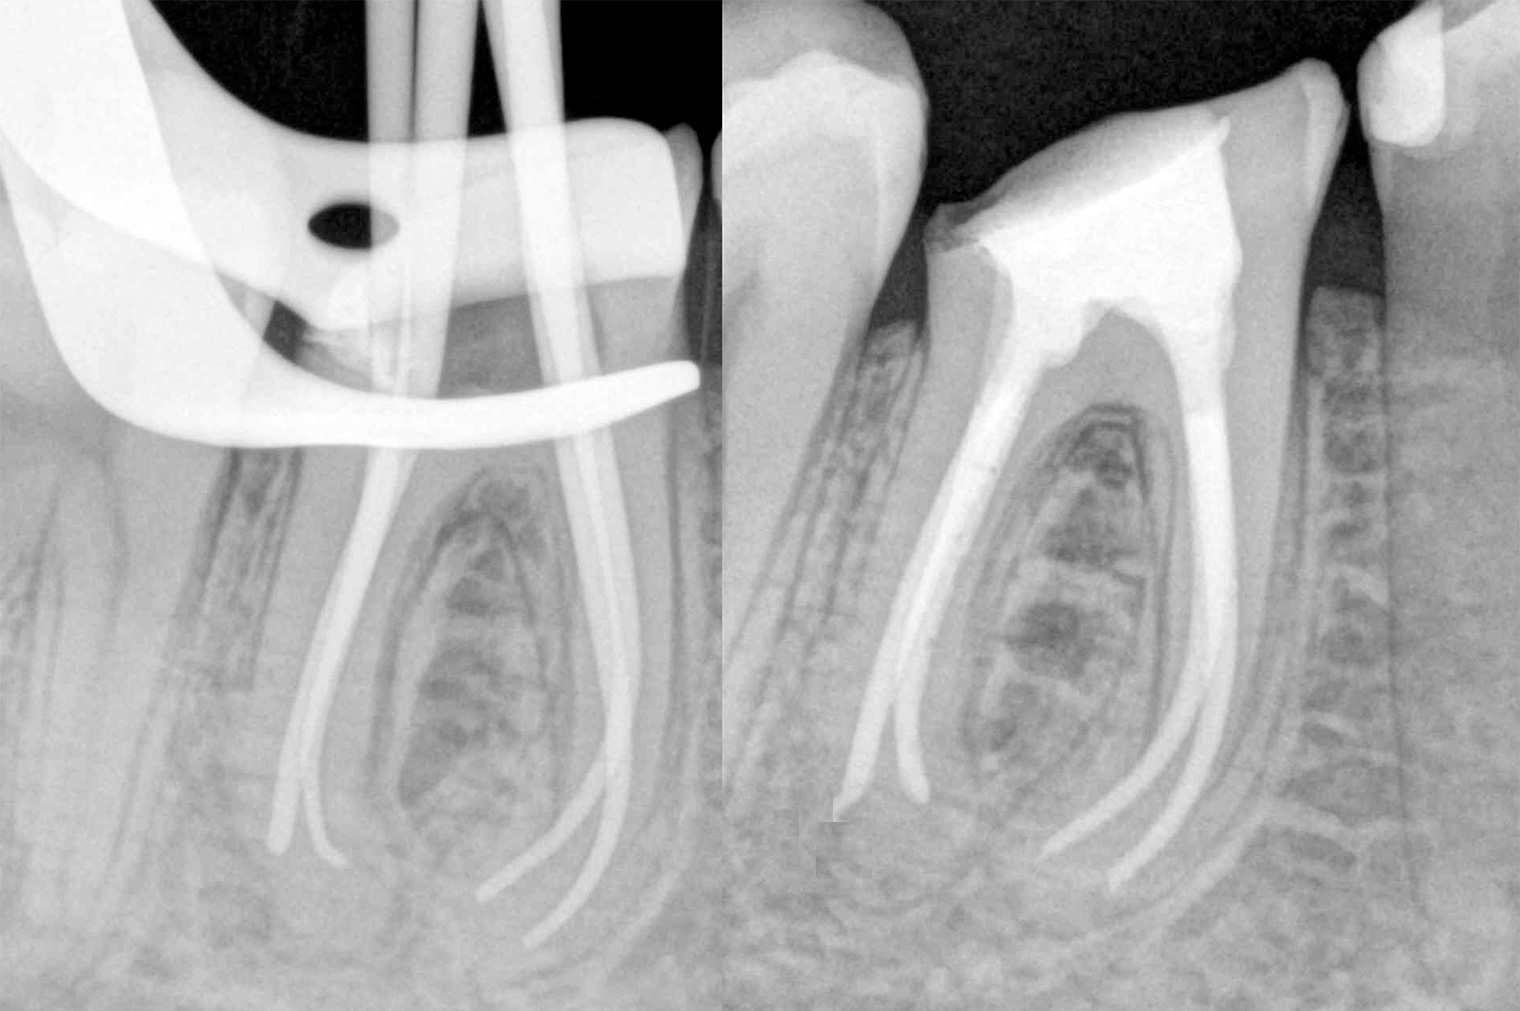

いなば歯科では歯科用CTやマイクロスコープ(歯科用顕微鏡)を使用し「出来るだけ自分の歯を残していく治療」を行っております。